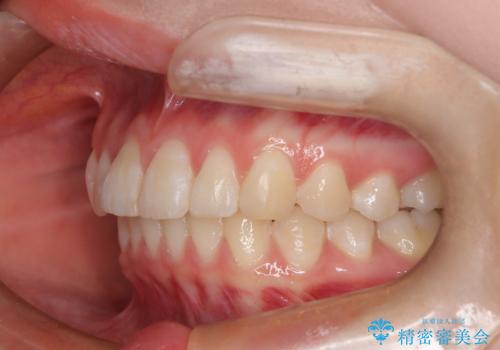

前歯のガタつきを治したい 翼状捻転マウスピース矯正

- 上顎前歯の突出、がたつき(翼状捻転)を主訴に来院されました。当院では総合歯科医療が可能であるため、矯正前処置として虫歯治療・歯周治療、親知らず抜歯を施行しました。その後、非抜歯かつ口元が出ないようなマウスピース治療を行いました。仕事柄、1日の装着時間が短くなってしまう時期もありましたが、患者様と相談しながら問題なく終了しています。